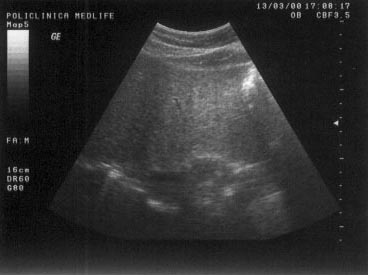

Figura 20. Delimitare neta intre ficat si rinichi. |

Figura 21. Scleroza renala - rinichiul drept prezinta contur neregulat si este imprecis delimitat. |